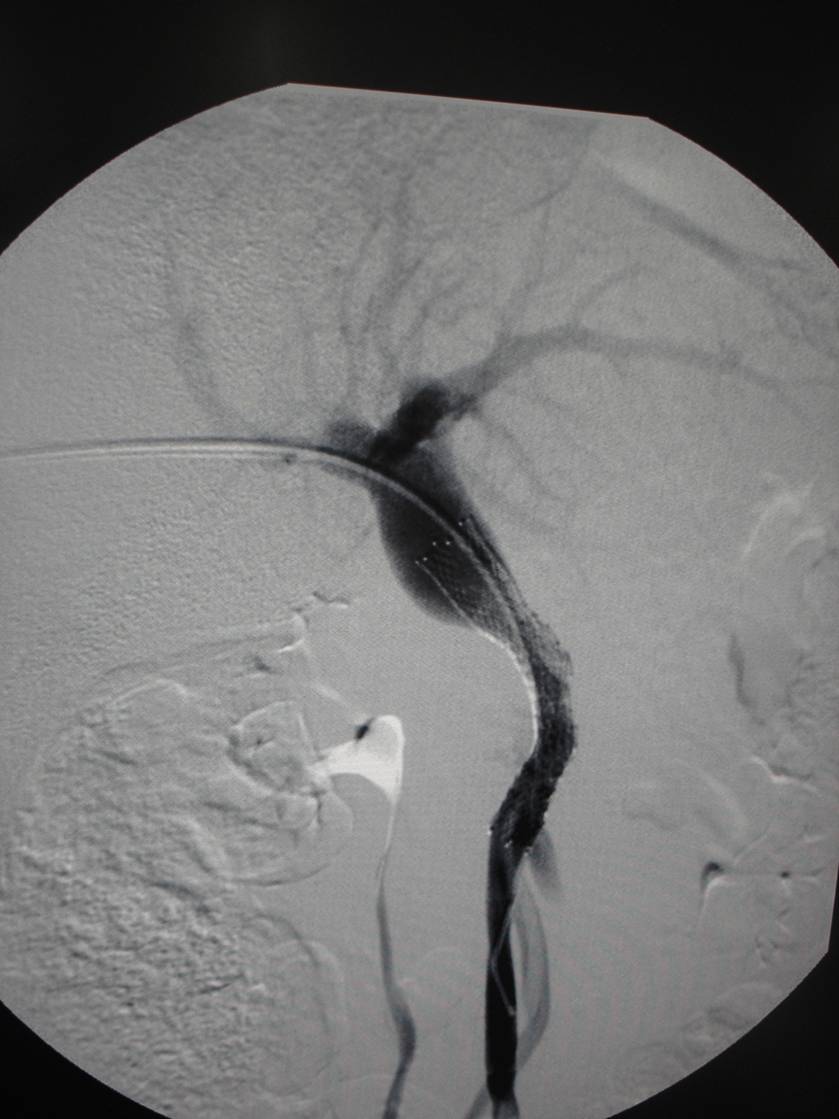

经全科讨论并请普外科、介入科会诊后,考虑慢性胰腺炎所致门静脉狭窄、区域性门脉高压,周围迂曲的侧枝循环导致胆肠吻合口处多发血管扩张并出血。患者转入介入科门静脉造影见门脉远端重度狭窄,用球囊扩张狭窄段,并自肠系膜上静脉及门静脉植入支架。